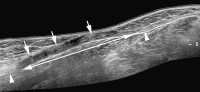

Abbildung 6: Sonographischer Längsschnitt ("Extended field of view"-Sonogramm) durch den Nervus peronaeus bei einem Patienten nach Kniegelenksluxation mit Ausbildung eines "Neuroma in continuity". Der Nerv (Pfeilspitzen) ist bei erhaltener äußerer Hülle langstreckig aufgetrieben (Doppelpfeil) und von mehreren Traktionsneuromen (Pfeile) durchsetzt.

Abbildung 7: Sonographischer Längsschnitt durch den Nervus radialis (Pfeilspitzen) bei einem Patienten mit Radialisparese nach operativer Versorgung einer Humerusschaftfraktur. Der Nerv wird durch die vom Knochen etwas abstehende Platte (kurze Pfeile) abgedrängt und komprimiert (langer Pfeil).